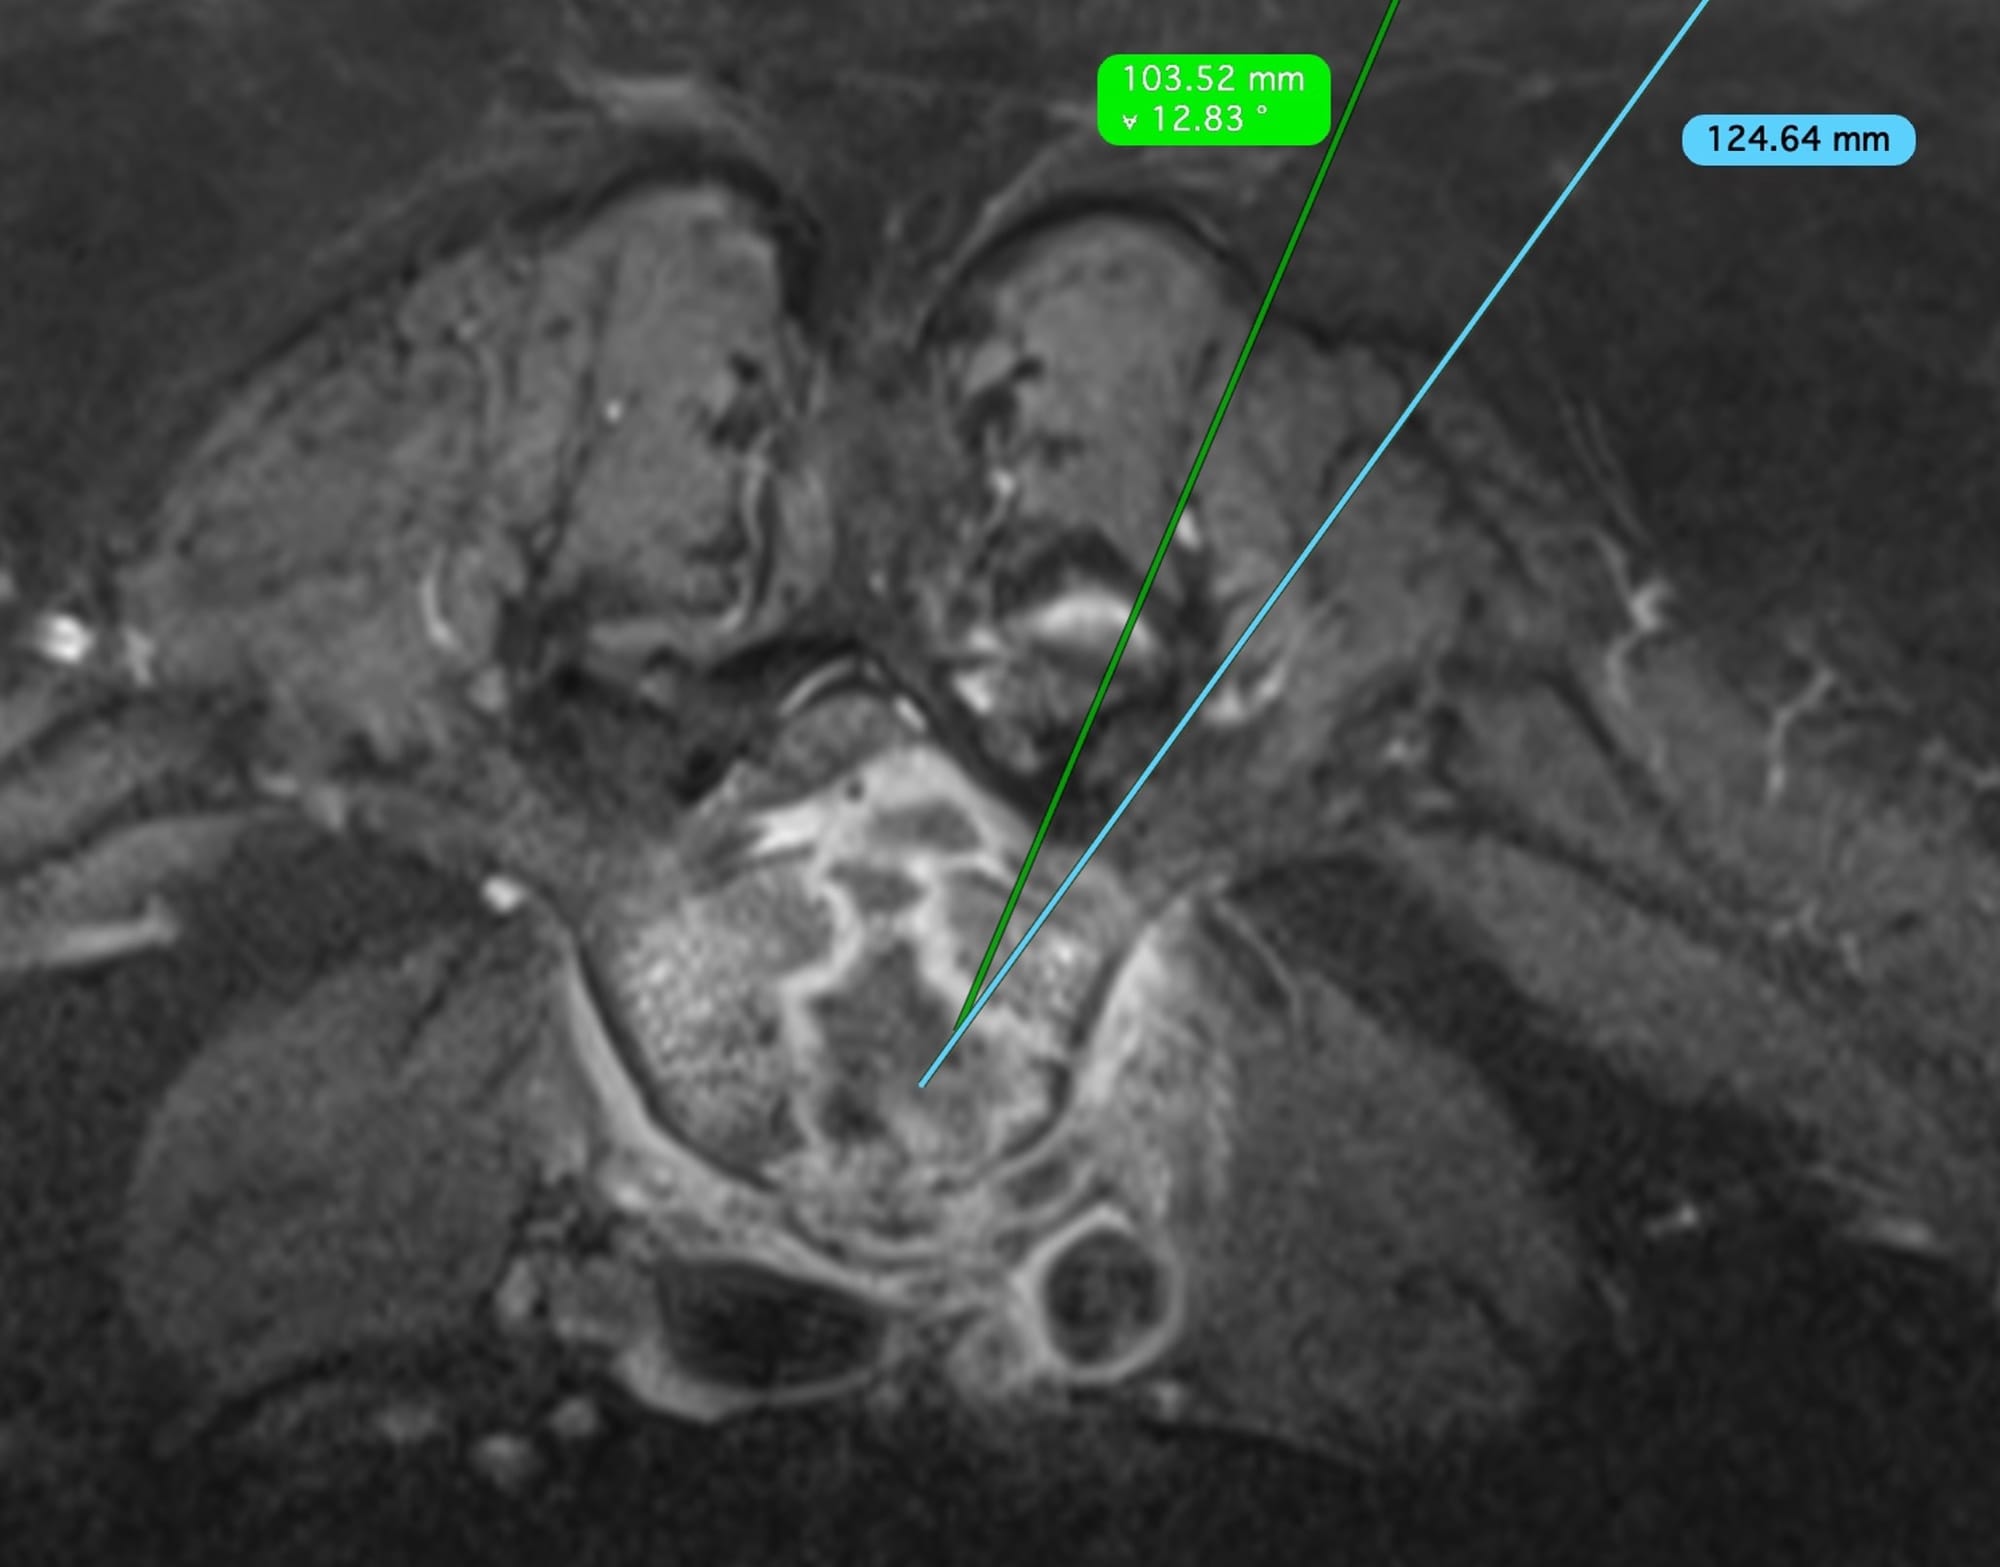

She was referred for a biopsy. On the MRI, it seemed a transpedicular approach may be possible, but once she was prone, the only approach was through the facet joint.

The video describes the case, the use of the transfacet joint approach and other similar cases.